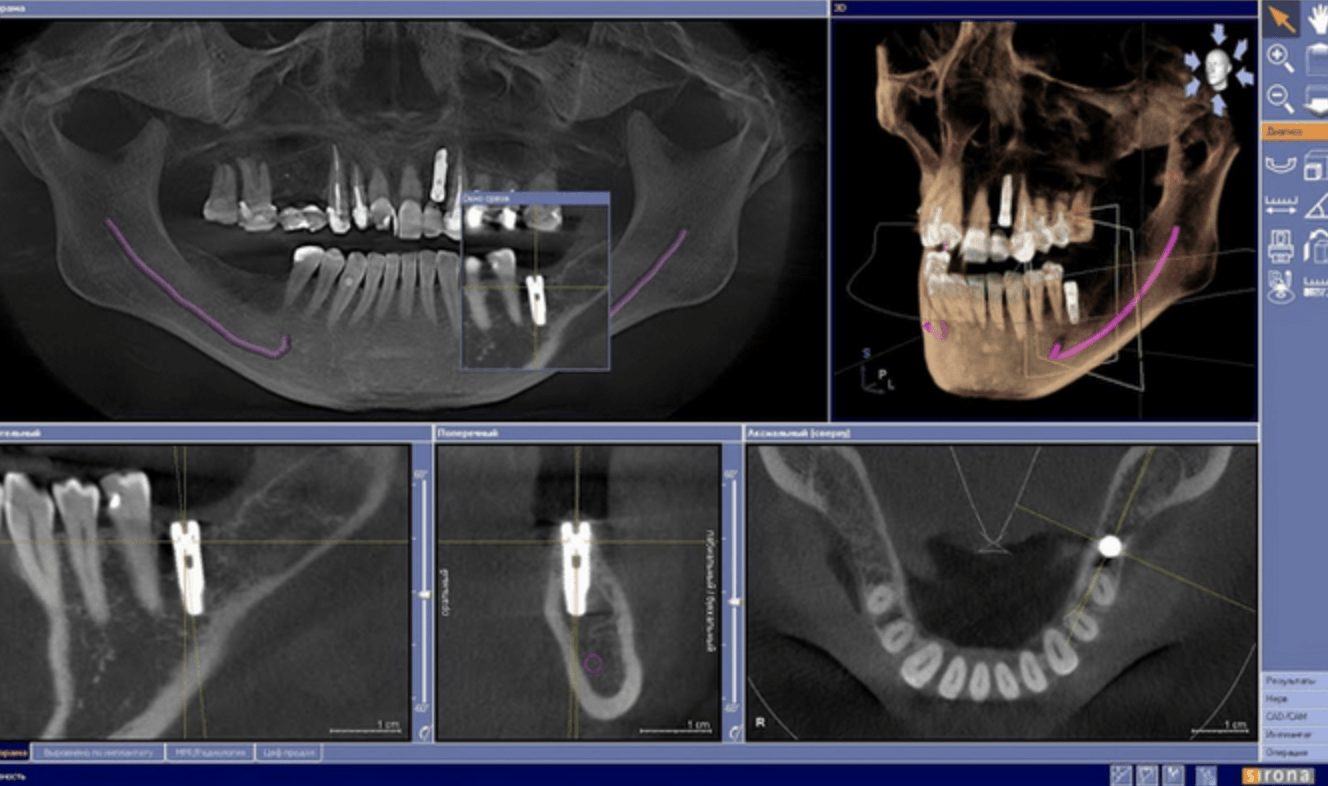

Konusinio pluošto kompiuterinė tomografija (CBCT arba kitaip vadinama 3D)

Konusinė (3D) tomografija

Gaunami trimačiai vaizdai, ypač tiksliai atkartojantys dantų ir žandikaulių anatomiją, parodo visus anatominius ypatumus bei uždegiminius procesus, leidžia tiksliau parinkti gydymo taktiką.